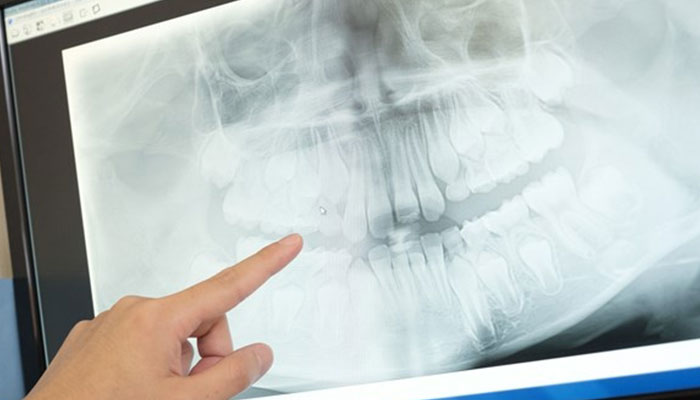

歯科ではレントゲンを撮ることがよくあります。

レントゲンはその直接目で見えない部分の情報を得るために行う検査です。レントゲンでわかることには主にこのようなことがあります。

むし歯の進行度、詰め物やかぶせ物に二次むし歯の原因となる隙間や段差ができていないか、また、その下にむし歯ができていないかなどの確認を行います。

むし歯が進行すると根っこに炎症を起こしたり、膿がたまったりすることがあります。また、歯冠部や根っこの割れやひびを確認することができます。

歯周病は進行するにつれ、歯と歯肉がはがれて隙間が大きくなり、歯肉の下にも歯石がつきます。また、歯を支える顎の骨が次第に吸収されて歯がグラグラになり、最後には歯が抜けてしまいます。レントゲンは、そのような歯周病の進行状態の確認に有効な手段です。

顎関節のズレや変形などを確認し、顎がカクカク鳴ったり、痛みが生じたりする原因を調べることができます。

その他、歯肉の下に埋まっている歯の確認や歯並びなど、さまざまな情報をレントゲンから得ることができます。